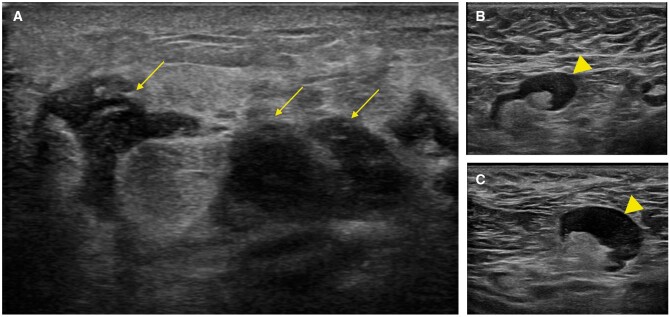

Idiopathic granulomatous mastitis (IGM) is an uncommon benign disease thought to have an autoimmune origin. After massive vaccination against COVID-19, mRNA vaccines have been associated with various possible adverse effects. Among those involving the breast, the most common are ipsilateral axillary lymphadenopathies and transient breast oedema. We present the case of a young woman who developed IGM after mRNA vaccination against COVID-19. We describe the clinical and imaging findings and management of this case, discussing the evidence for a possible link between vaccination and the development of this uncommon inflammatory process and underlining the importance of including this entity in the differential diagnosis in this scenario.